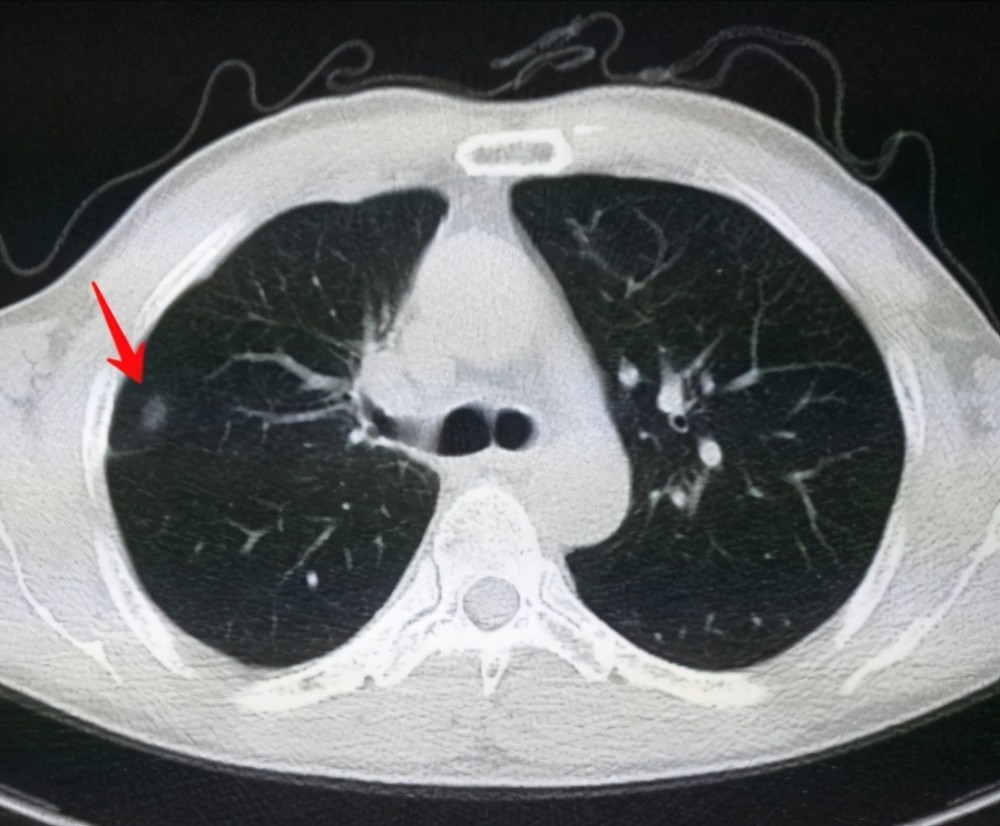

肺結(jié)節(jié)是一種常見的肺部疾病,其發(fā)病率逐年上升,雖然肺結(jié)節(jié)多數(shù)情況下是良性的,但也有可能惡化為肺癌,了解肺結(jié)節(jié)的形成原因?qū)τ陬A(yù)防和治療具有重要意義,本文將為您詳細(xì)解析肺結(jié)節(jié)的形成機(jī)制。

2、遺傳因素

遺傳因素也是肺結(jié)節(jié)形成的重要因素,研究表明,家族中有肺癌或肺結(jié)節(jié)病史的人群,其患病風(fēng)險(xiǎn)較高,遺傳缺陷可能導(dǎo)致肺部細(xì)胞異常增生,從而引發(fā)肺結(jié)節(jié)。